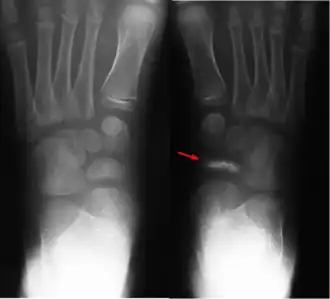

Ziekte van Köhler bij een 8 jaar oud meisje. Bij het pijltje is te zien dat het bot bijna verdwenen is. (Vergelijk de andere, gezonde voet.) | ||||

In de vroege fase zijn de röntgenfoto's nog normaal. Afwijkingen (botsclerose) zijn röntgenologisch pas zichtbaar tijdens de fase waarin het bot zich alweer aan het herstellen is, de 'reparatiefase'.